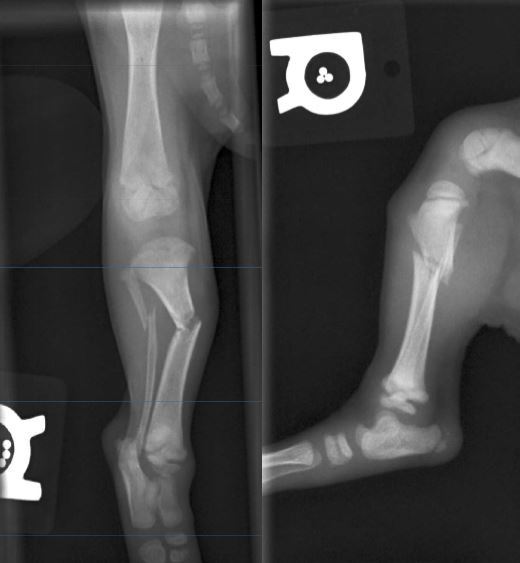

5

Q

1 year old DSH, 4.5kg

HBC 24 hours ago.

Classify and assess fracture, and give repair options

Severely comminuted femoral fracture

and

Short oblique tibial fracture

Fx score= 5

Repair: 2 ESFs (Type 1A), on femur + cerclage wire and IM pin